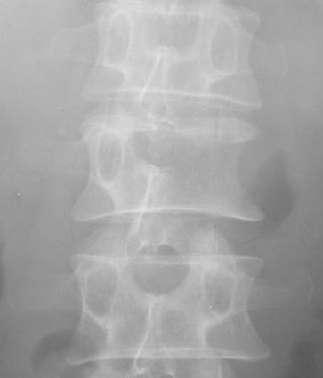

三、脊柱结核:临床特点:1、腰椎多见;2、多累及相邻或多个椎体,附件较少累及

X线表现:1、骨质破坏和脊柱承重 — 椎体塌陷变扁或楔形;2、累及椎体上下缘及邻近软骨板和椎间盘 — 椎间隙变窄或消失,椎体嵌入融合,后突畸形;3、冷脓肿形成,可钙化:腰大肌脓肿(腰椎)、椎旁脓肿(胸椎)、咽后壁脓肿(颈椎)

【影像学检查】X线平片表现以骨质破坏和椎间隙狭窄为主。中心型结核的骨质破坏集中在椎体中央,侧位片比较清楚。很快出现椎体压缩成楔状,前窄后宽。边缘型结核的骨质破坏集中在椎体的上下缘,表现为进行性椎间隙狭窄,并累及邻近两个椎体。可见脊柱侧弯或后凸畸形。椎旁软组织阴影(腰大肌)增宽。